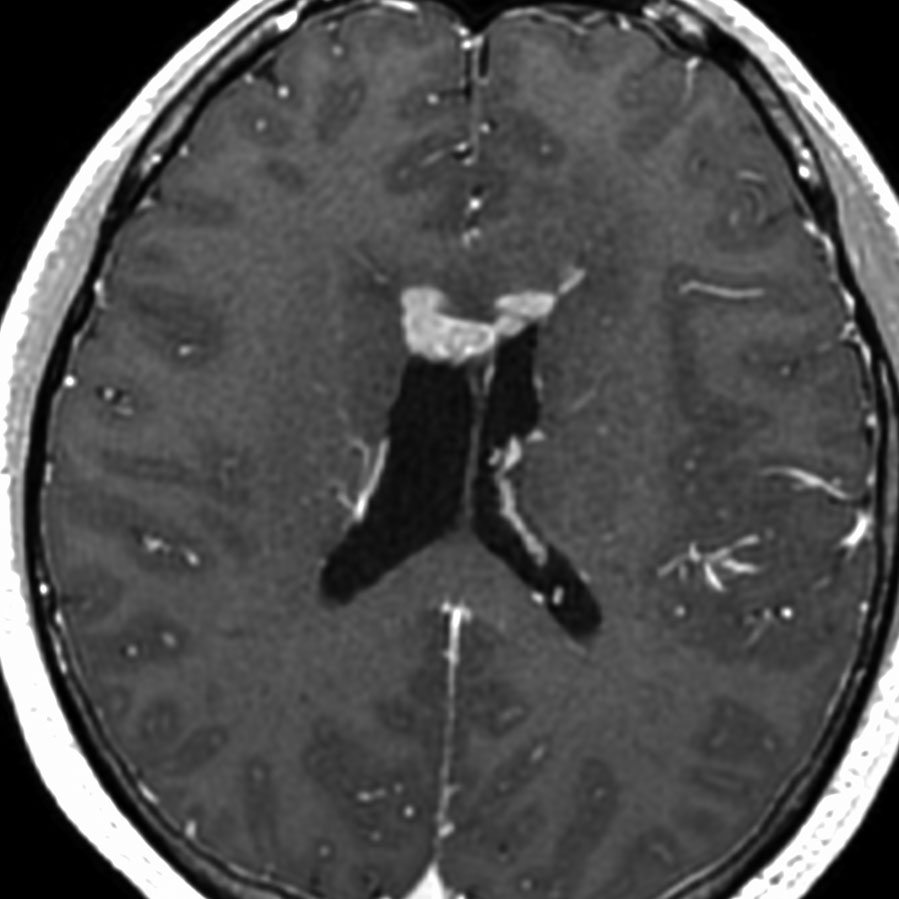

ガドリニウム増強では,前頭葉腫瘍というより,側脳室壁にベトベトくっついているような腫瘍です。germinoma特有のsubependymal infiltration像を示します。

左はICE化学療法 (IFO/CDDP/VP-16)前,右は1コース終了後です。腫瘍は顕著に縮小してgerminomaとして普通の化学療法反応性を示します。また,松果体と下垂体には腫瘍はありません。

ICEを3コース行なって腫瘍は完全消失して,前頭葉浮腫も消えました。その後に,全脳照射 25.2Gy/14分割を加えました。無症状で復職することができました。